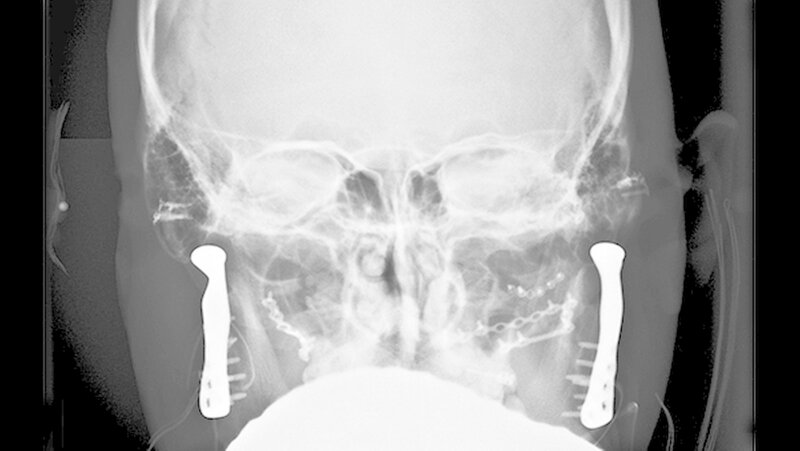

In der Folge entwickelte sich binnen fünf Monaten eine absolute Mundöffnungsbehinderung. Die SKD betrug null Millimeter. Passend zur klinischen Symptomatik zeigten sich radiologisch die Zeichen einer knöchernen Ankylose der Kiefergelenke beidseits Typ III nach Sawhney [1986] (Abbildung 1a-d).

Vor der definitiven Fixierung der Prothesen wurden Dummys als Test eingesetzt, um eine optimale Positionierung der passgenauen finalen Prothesen zu erreichen (Abbildung 2 bis 9). Abbildung 10 a und 10b zeigen die postoperative Röntgenkontrolle.